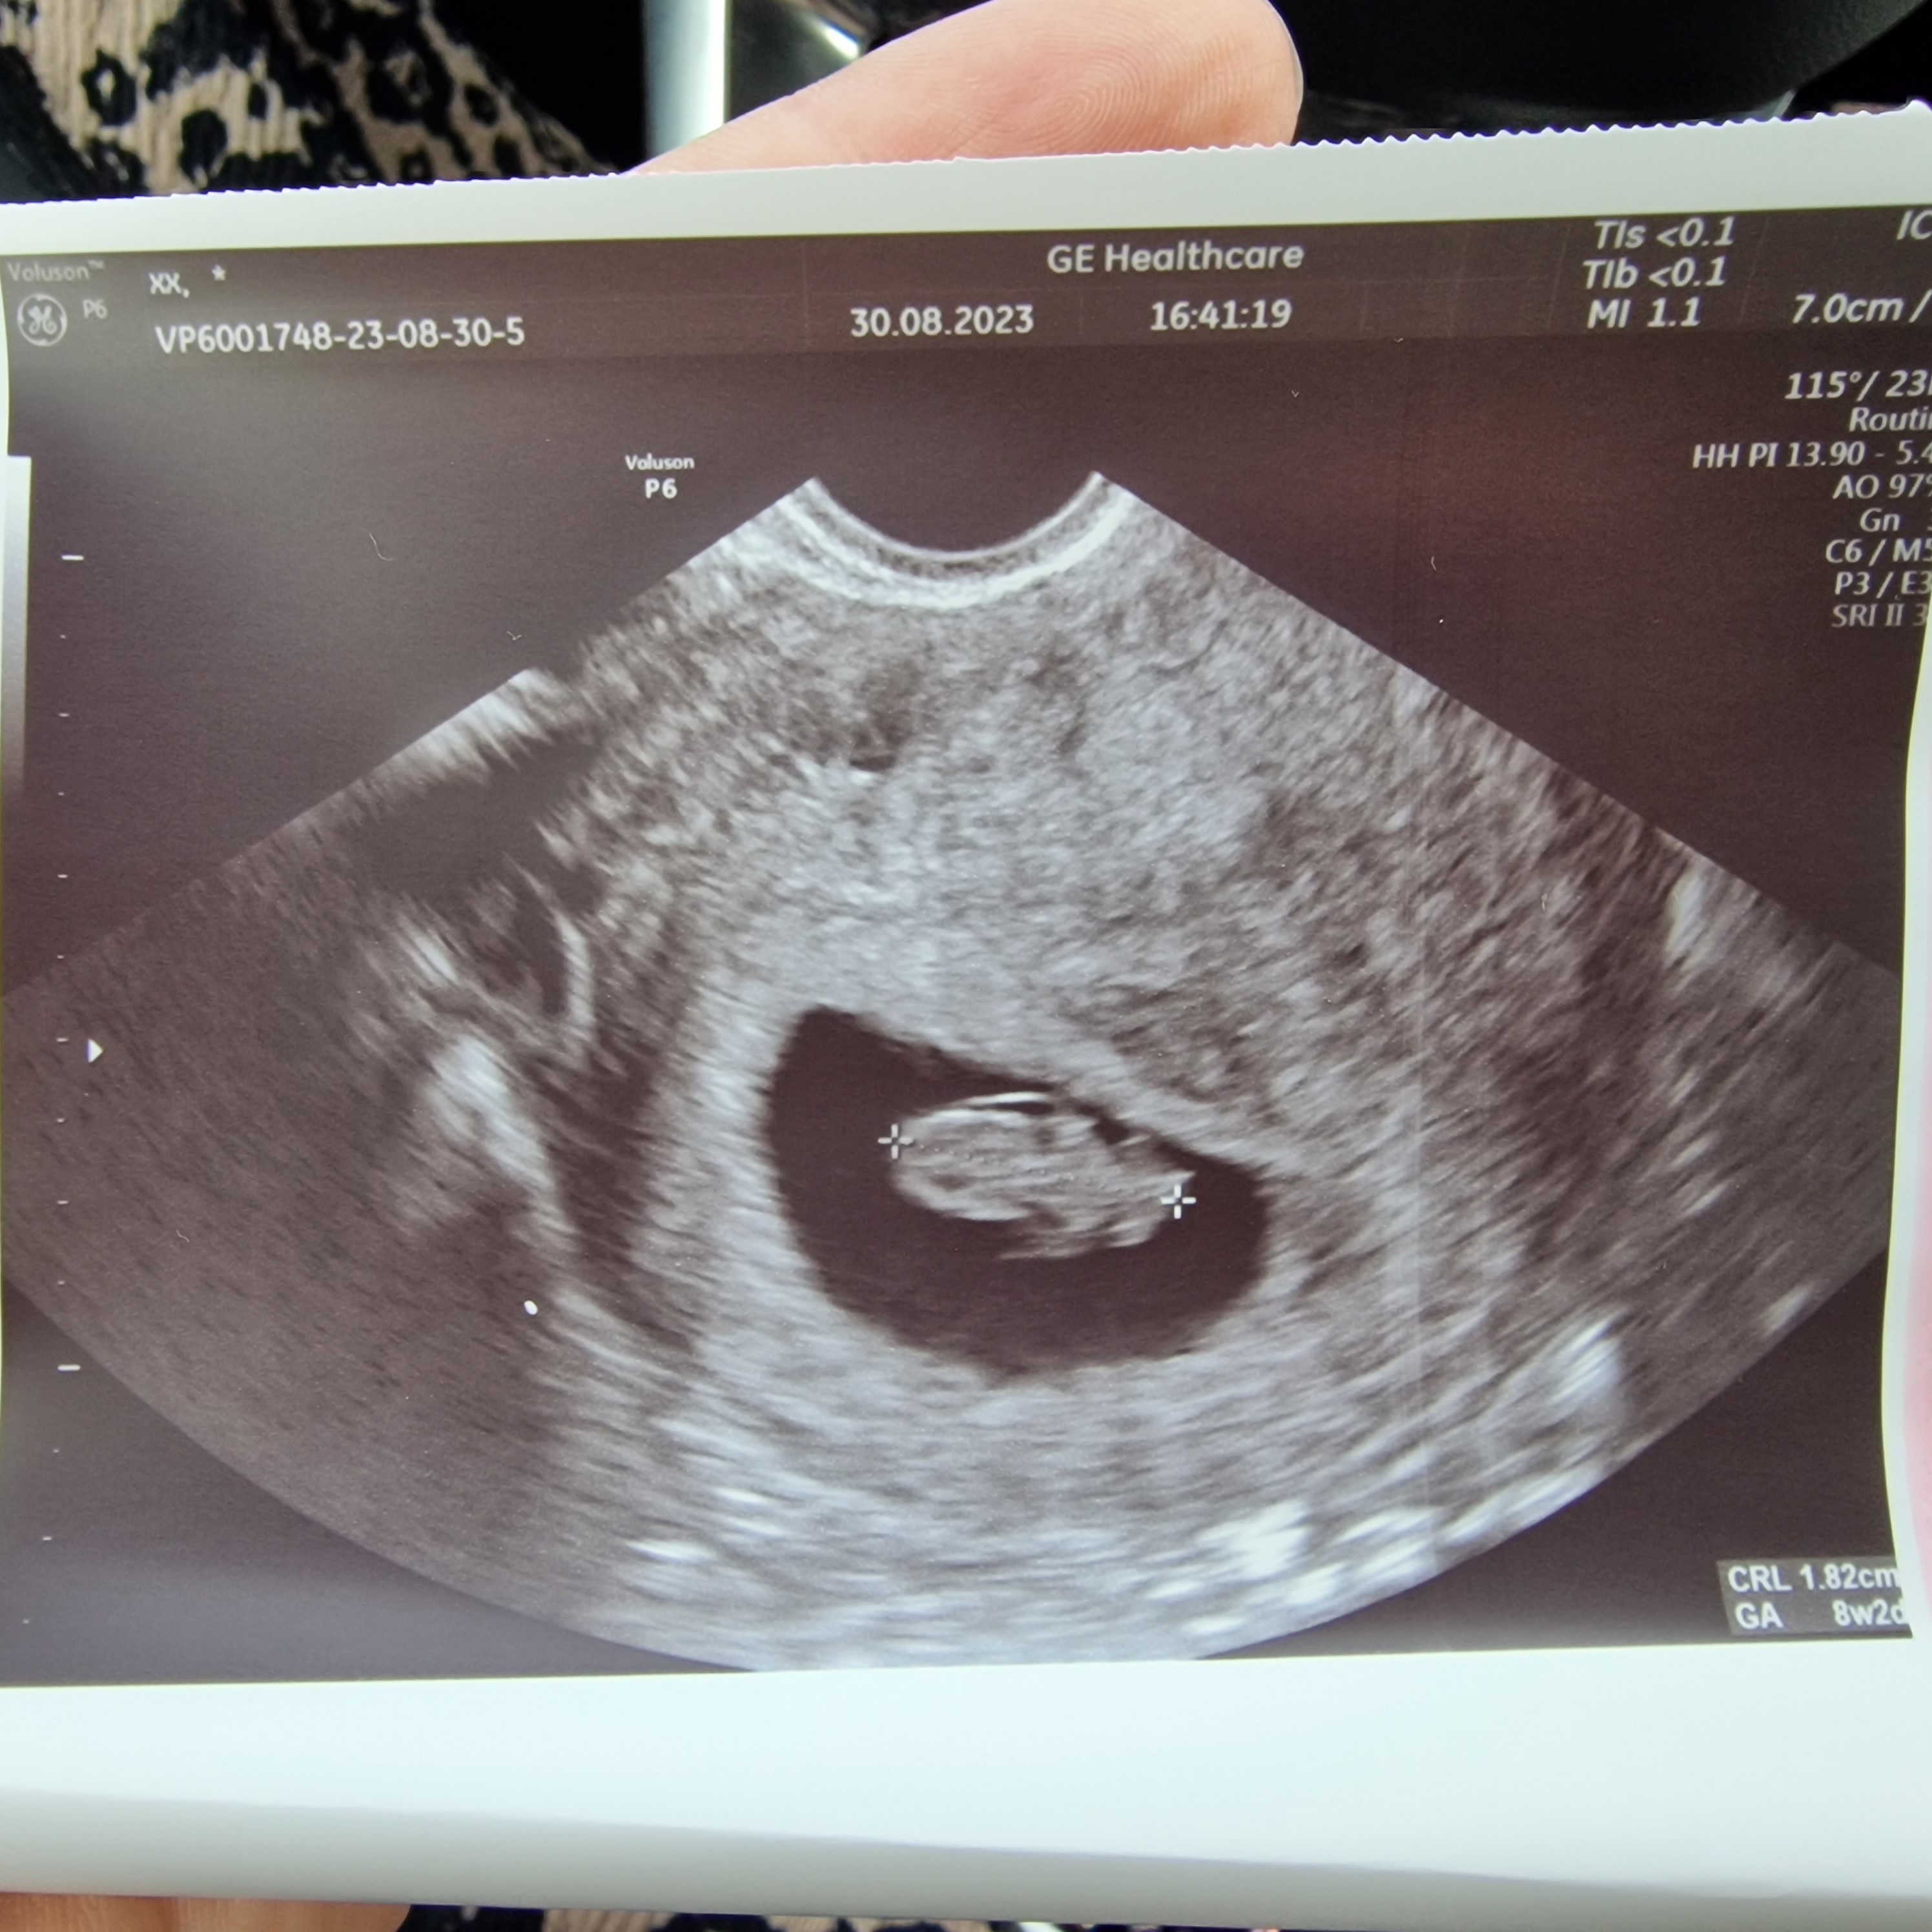

Jestem już po wizycie. Z usg dzisiaj 8+2 a z om 8+1. Mam być dopiero za miesiąc, 27.09 u mojej ginekolog a 28.09 mam prenatalne. Pani Doktor powiedziała że ciąża ma się świetnie, serduszko pięknie pracuje i wystawiła mi jeszcze skierowanie na morfologie i mocz. Tak więc trochę się uspokoiłam i zaczynam kolejne odliczanie 😅

Załączniki

• 20230830_171741.jpg

20230830_171741.jpg

902,6 KB · Wyświetleń: 107